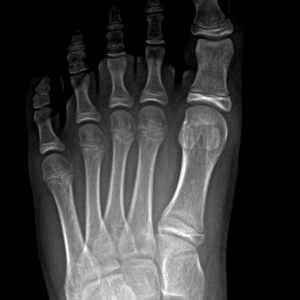

Pediatric Radiographs